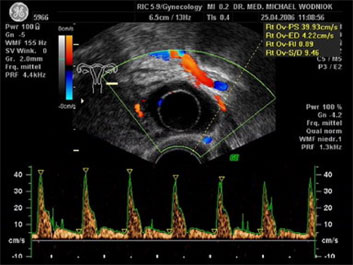

Hochauflösende Ultraschalluntersuchungen in Kombination mit der 3D-4D Technik werden in unserer Praxis routinemäßig durchgeführt. Dabei werden im Rahmen der Vorsorgeuntersuchung, sowie bei reinen vorsorglichen Ultraschalluntersuchungen auf Wunsch, auffällige Tastbefunde und noch unentdeckte Befunde weiter sonografisch abgeklärt. Bei zweifelhaften Befunden der Brüstdrüsen oder von Organen der inneren Genitalien kann der zusätzliche Einsatz der Farbdopplertechnik sehr hilfreich sein. Dabei stellt diese Technik bildlich sehr genau den Blutfluss, die Flussgeschwindigkeit, den Blutflusswiderstand sowie die Blutflussrichtung aller Blutgefässe dar. Die Interpretation dieser Ergebnisse fließt als zusätzlicher „Marker“ in die Entscheidung für das weitere klinische Vorgehen ein. Ein zunächst als völlig unauffällig eingestufter Ultraschallbefund eines zystischen Befundes im Eierstock wird bei einem unerwartet auffälligen Blutfluss an der inneren Zystenwand eine zeitnahe weitere Abklärung zu Folge haben. ![]() ![]() ![]() ![]() |